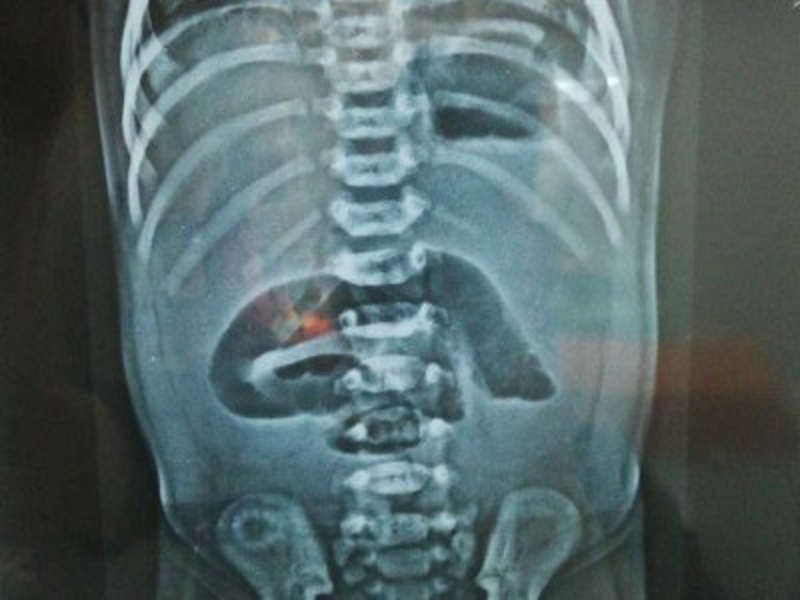

The baby was admitted, and a nasogastric tube was passed which yielded greenish aspirate. X-ray abdomen erect showed a few dilated loops of small bowel in the mid-abdomen; gas in the colon and rectum was not visualized (Fig.1). Ultrasound of abdomen documented gaseous distension of the small bowel. All baseline investigations were done which turned out as normal.

Figure 1

X-ray showing intestinal obstruction.